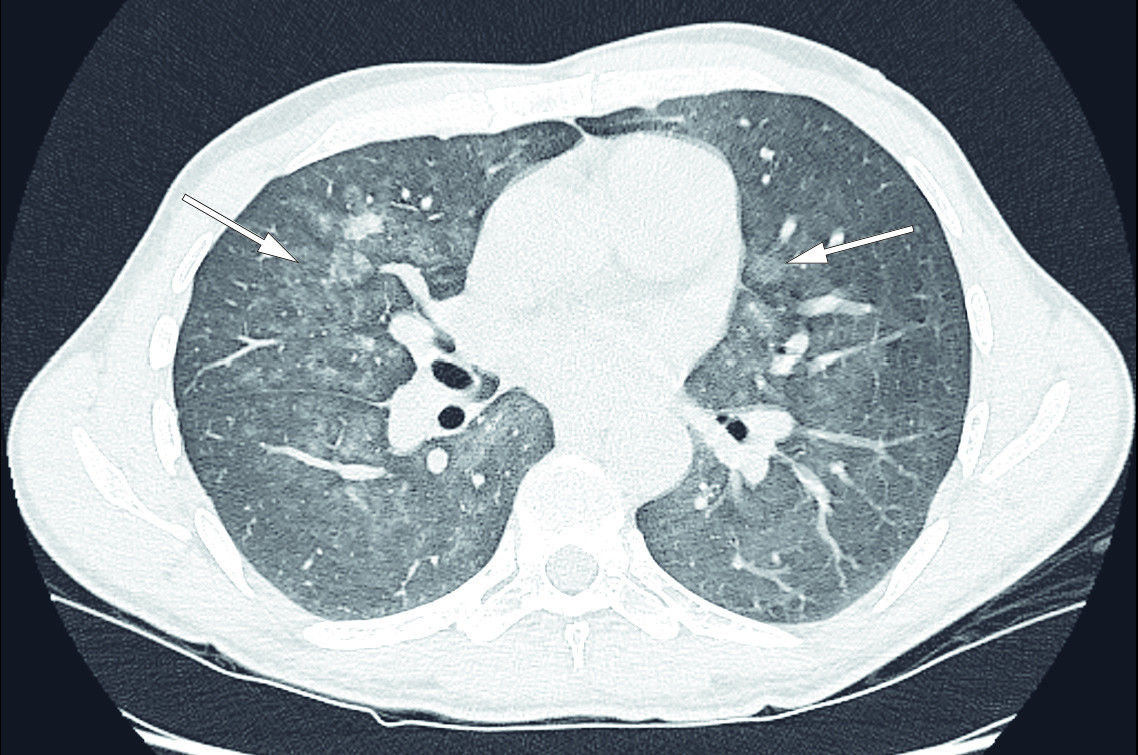

CT av brystkassen viste nå at det i løpet av fire uker var tilkommet bilaterale, flekkvise mattglassfortetninger med utsparing av lungetoppene og helt basale deler av lungene (figur 2). I tillegg til differensialdiagnosene beskrevet på PET-CT ble interstitielle sykdommer og blødning grunnet vaskulitt foreslått som differensialdiagnoser.

Pasienten ble raskt dårligere og ble innlagt på lokalsykehuset fem dager senere. Dagen etter ble han overflyttet til lungemedisinsk avdeling ved et større sykehus for videre utredning. Ut fra funnene som forelå på dette tidspunktet, ble interstitiell lungesykdom mistenkt. Til tross for forhøyede ACE-verdier passet det kliniske og radiologiske bildet dårlig med sarkoidose. Infeksjoner, inkludert Pneumocystis jiroveci-pneumoni, ble også fortløpende vurdert. Det var ingen holdepunkter for at pasienten hadde nedsatt immunforsvar.

Ny CT-undersøkelse av brystkassen tatt cirka seks uker etter første innleggelse på lokalsykehus viste tydelig progresjon av bilaterale lungefortetninger, og det var ikke holdepunkter for lungeembolisme. Lungefunksjonsundersøkelser viste ytterligere reduksjon av lungevolumer og fortsatt redusert diffusjonskapasitet.